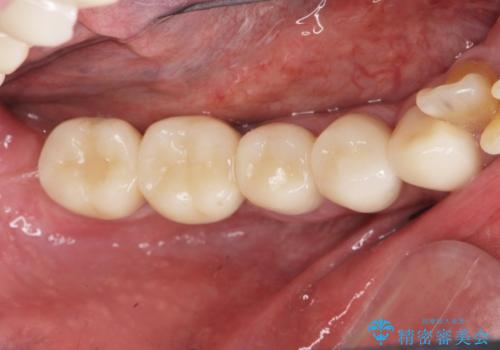

銀歯が口腔内からなくなり審美的になっただけでなく、歯ブラシのしやすさや噛み合わせの安定、口臭の減少など、良好な結果を得ることができました。